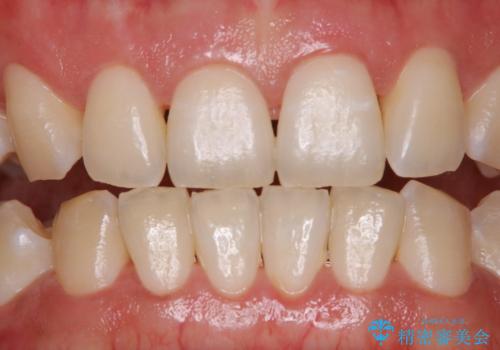

ホワイトニングせずにPMTCで明るい口元に

- ホワイトニングを考えているとのことで久しぶりに来院された方です。歯石やプラークの付着があったため、まずはPMTC60分コースを行いました。

施術後には、現状で満足とのことだったため今後は定期的なクリーニングを行っていくこととなりました。

PMTCでは、プラークや歯石、着色などを徹底的に除去します。